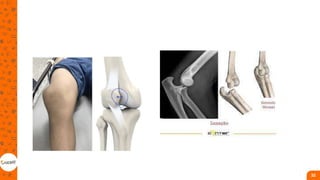

Fratura ao redor do joelho

• Grande morbidade;

• Geralmente cirúrgico;

• reconstrução anatômica da

superfície articular, reparo dos

tecidos moles lesionados,

restauração do eixo, congruência

e estabilidade articular. Nas

fraturas distais do fêmur, o

tratamento padrão é a redução

aberta e a fixação interna.

• Na patela, é possível um

tratamento não operatório em

fraturas fechadas e sem desvio

com um mecanismo extensor

íntegro;

• a maioria das fraturas requer

redução aberta e osteossíntese;

• aramagem em banda de tensão

é a técnica mais utilizada;

• Patelectomia;